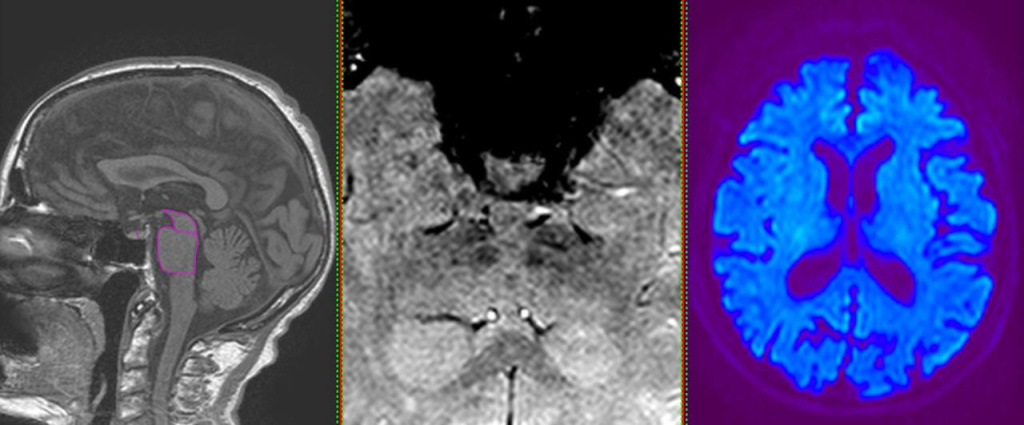

МРТ головного мозга и оценка маркеров нейродегенерации при болезни Паркинсона — это высокоточный метод диагностики, позволяющий выявить изменения в структурах мозга, характерные для болезни Паркинсона.